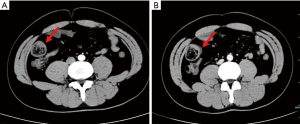

Case 1 was a 42-year-old woman referred to our hospital because of abdominal pain and melena lasting 3 months. On assessment, the patient appeared apprehensive and pale. Physical examination revealed tenderness in the right lower quadrant, with no palpable lump. Laboratory investigations revealed a hemoglobin level of 85 g/L. Intussusception was suspected and confirmed on abdominal ultrasound. Computed tomography (CT) imaging revealed an ileal mass, intussusception with thickening of the colic wall, and slight proximal intestinal dilation (Figure 1). An emergency laparotomy was performed immediately which revealed a submucosal lipoma (measuring 5 cm × 4 cm) causing intussusceptions; this was subsequently removed along with part of the small intestine. Pathologic examination suggested an ileo-ileal intussusception secondary to a 5 cm submucosal lipoma with HP. The patient recovered uneventfully and was discharged 8 days after the operation.